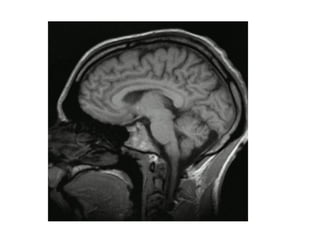

O ENCÉFALOO ENCÉFALO

Bulbo raquídeo: control de

funcións involuntarias como o

ritmo cardiaco e respiratorio.

Cerebelo: coordinación dos

movementos

Cerebro: centro de control

superior no que reside o control

dos actos voluntarios, intelixencia

e a memoria

Tronco cerebral e hipotálamo: control das

conductas máis primitivas, instinto,

emocións...

Hipofese: glándula endócrina que controla o

sistema endócrino

Bulbo olfatorio: nel reside o sentido do

olfato